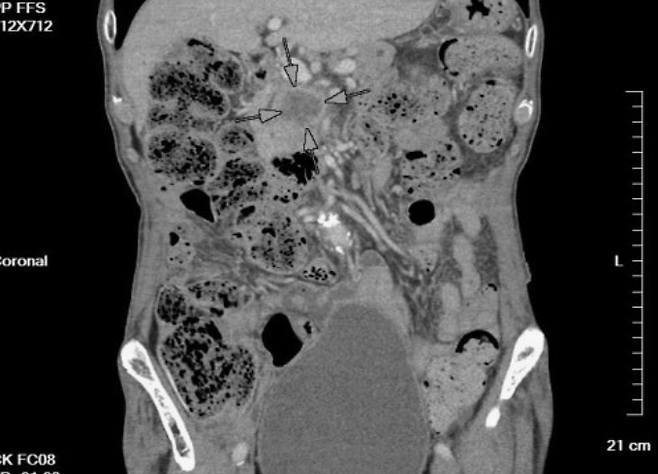

췌장암은 조기 발견율이 매우 낮고, 증상이 나타나면 이미 진행된 경우가 많아 수술 가능성이 적습니다. 하지만 위 증상 중 하나라도 의심된다면 반드시 전문의를 찾아 영상 검사(CT, MRI, 초음파 내시경 등)를 받아야 합니다. 조기 진단이 가능할 경우 생존율을 크게 높일 수 있습니다.